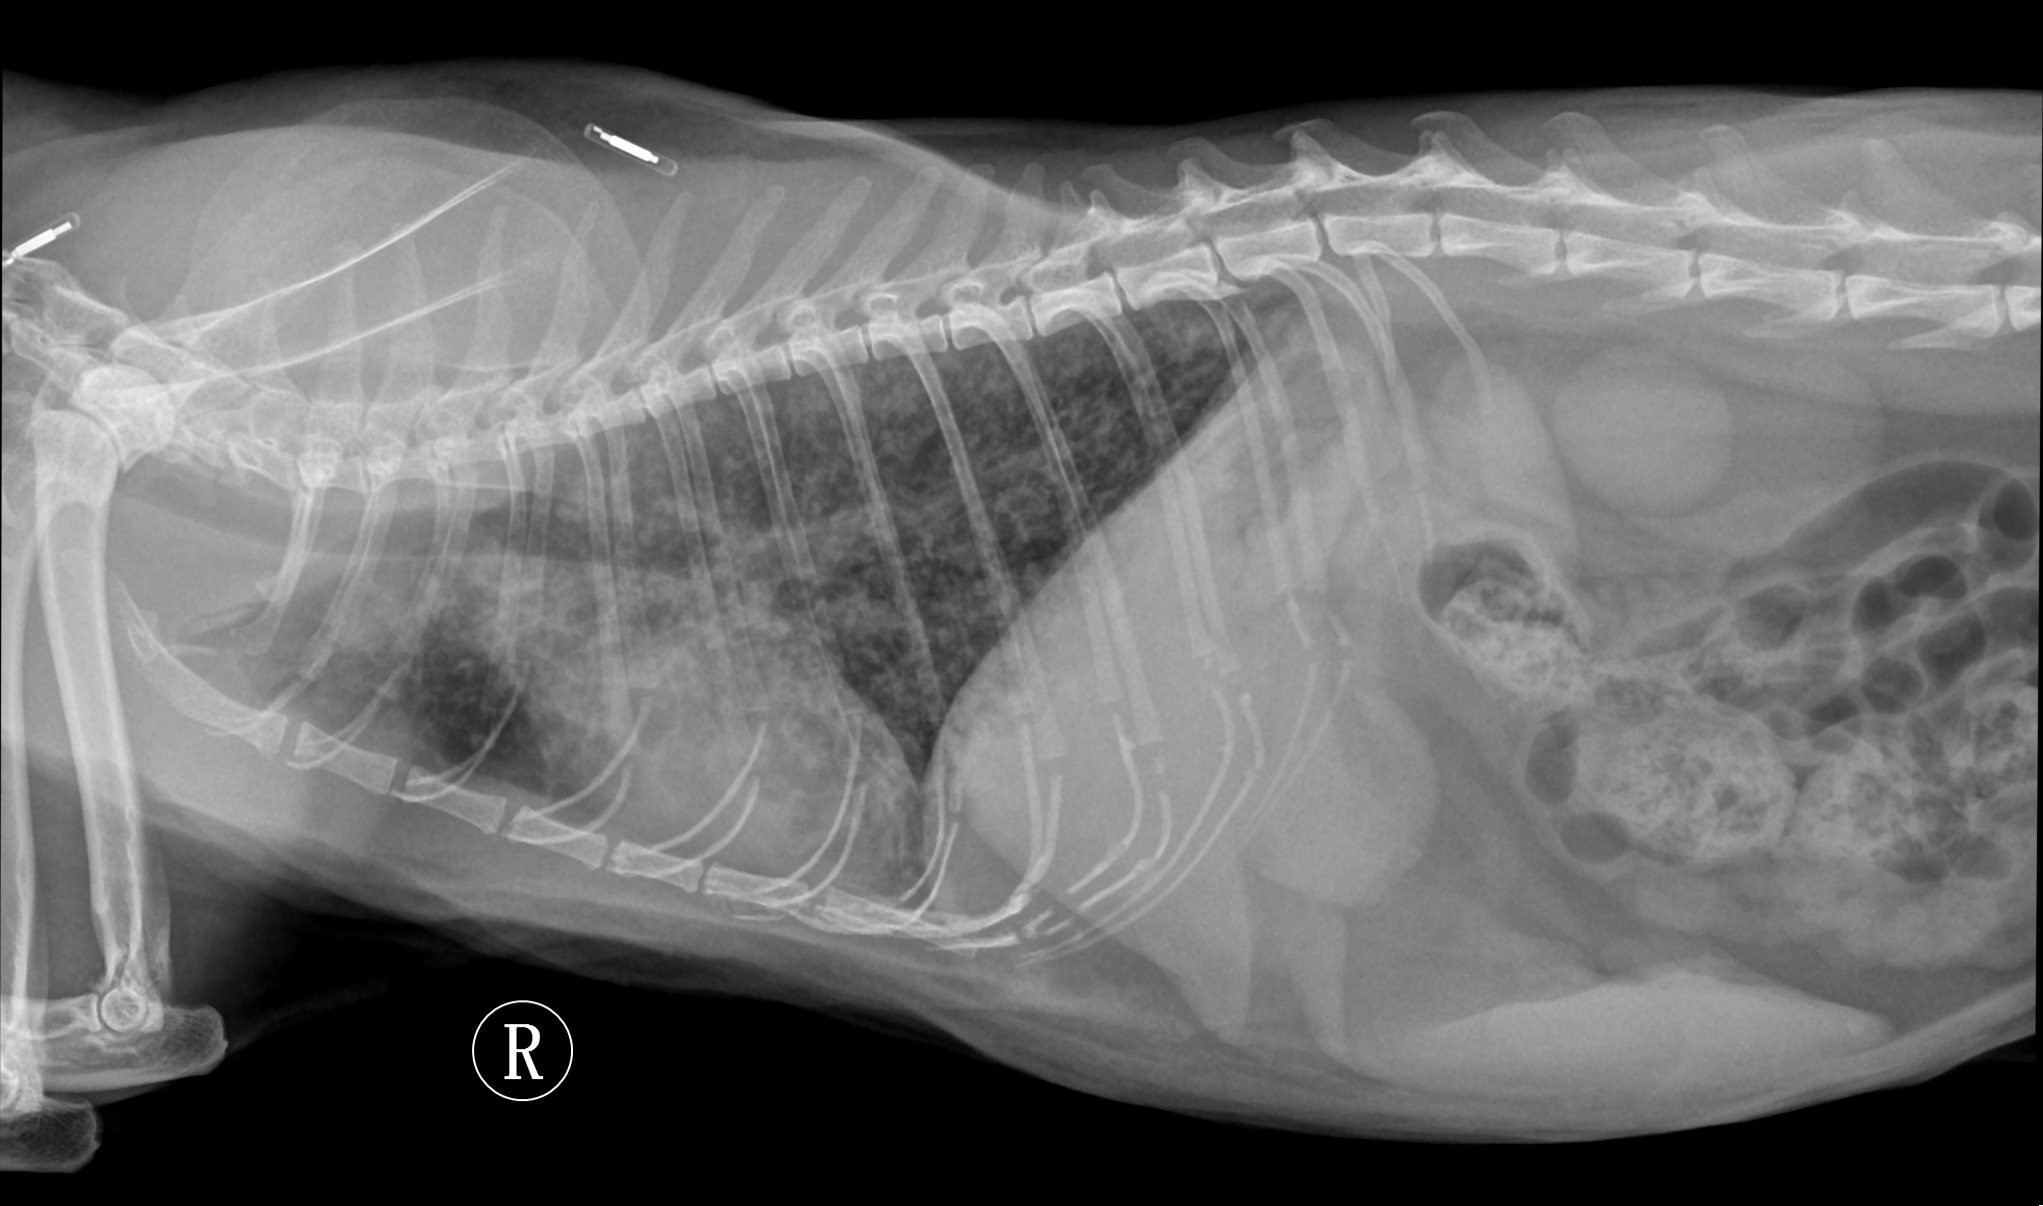

Radiology Support

Need a hand with radiographs, CT, MRI or US loops? We’ve got you covered. Our team provides detailed, high-quality reports to support you in managing your cases.

In addition to interpreting images, we can also provide imaging protocols for specialized CT or MRI studies (for example: urinary tract excretory contrast CT, lymphangiography, etc.). Let us know if you have questions about the imaging in advance.

Over the years, we’ve learned that imaging reaches its full potential when interpreted in context. That’s why for radiographs, CT, MRI, and ultrasound cases, our radiologist can collaborate with clinical specialists who can review the case in depth. After reviewing the images, the specialist can discuss the next steps with you—from further work-up to treatment planning.